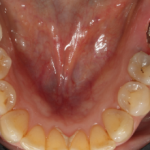

Le cas clinique met en évidence une insuffisance de volume osseux avec un axe implantaire défavorable en secteur postérieur, objectivée sur l’imagerie 3D et la radiographie panoramique, compromettant un positionnement implantaire axial conventionnel sans compromis prothétique.